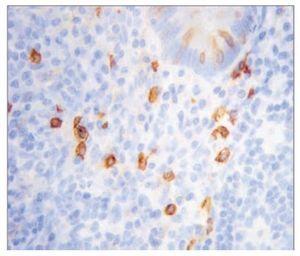

¿ Figura 5. Análisis histopatológico que determinó tumor estromal de alto grado con bordes quirúrgicos libres de lesión, con inmunohistoquímica para CD117.